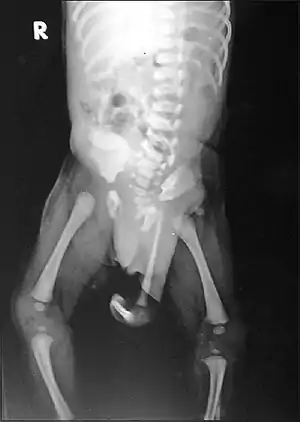

| Radiograph of a human child with polymelia | |